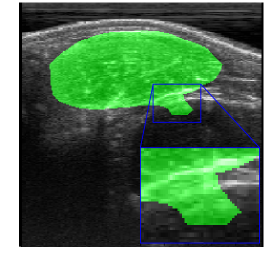

Rib Eye Area (REA). This image dataset consists of ultrasound images of the Longissimus dorsi muscle between the 11th and 13th ribs of cattle. The goal is to automatically calculate the rib eye area (REA), an important region for decision making during cattle breeding. The main challenge is the uncertainty in the REA annotation, since the image is noisy and even experts have difficulty in delimiting the borders of this region. Fig. 3 presents examples of images and the annotation made by a specialist. We can observe that some borders are absent and depend on the subjectivity and knowledge of the annotator. To evaluate the segmentation methods, 76 images with 309×213309213309\times 213 resolution were obtained and labeled by an expert. Due to the number of images, the division of the images in training and testing followed 5-fold cross-validation.

Refer to caption

Figure 3: Sample images from Rib Eye Area (REA) dataset.

REA dataset. This image dataset has high uncertainty during labeling due to noise from the ultrasound image. In some cases, the border of REA is not completely visible and must be estimated by the specialist. Therefore, the proposed approach becomes essential to obtain accurate segmentation at the edges. The segmentation examples in Fig. 6 show that the baseline was not able to define the REA correctly due to the uncertainty of the labeling. On the other hand, the proposed approach presents results close to the specialist in regions that the border needs to be estimated.